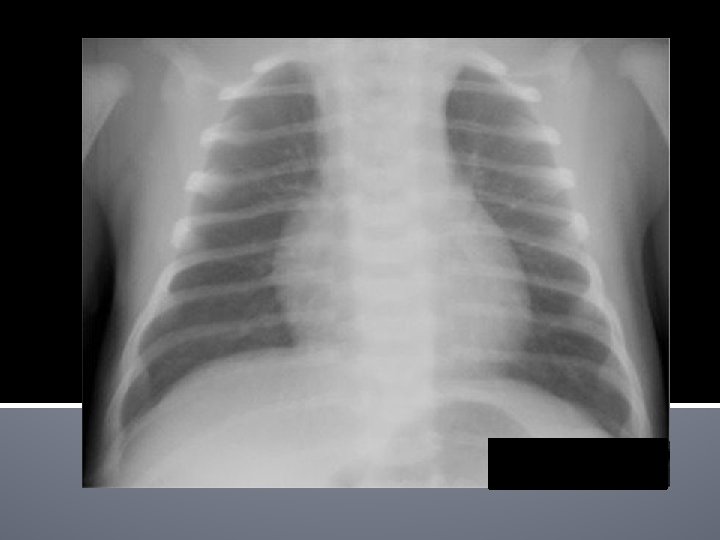

Atelectasis RML

Atelecasis RML